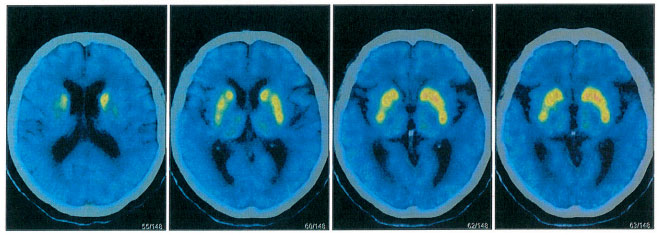

為了進一步鑒別診斷,張靜波主任團隊為患者進行了PET磁共振檢查(多巴胺轉(zhuǎn)運體、葡萄糖代謝、Aβ蛋白分子影像學鑒別),進一步鑒別帕金森病和老年癡呆。張靜波主任介紹,除了在惡性腫瘤的診斷、治療前評估與療效評估等應(yīng)用,PET在神經(jīng)系統(tǒng)疾病的診斷上也應(yīng)用廣泛。在腦顯像中,PET能提供病理生理學和分子水平信息,為神經(jīng)系統(tǒng)疾病(尤其是神經(jīng)退行性疾病和腦腫瘤等)的診療決策提供有力的證據(jù)。

▲ 檢查結(jié)果:多巴胺轉(zhuǎn)運體異常

PET影像結(jié)果示:腦部18F-AV45結(jié)果:雙側(cè)大腦半球皮質(zhì)Aβ(β-淀粉樣蛋白)未見異常沉積。腦部18F-FDG結(jié)果:雙側(cè)額葉、雙側(cè)尾狀核、中腦FDG代謝減低;雙側(cè)小腦FDG代謝減低。腦部11C- CFT結(jié)果:雙側(cè)尾狀核、雙側(cè)殼核前部、雙側(cè)殼核后部DAT(多巴胺轉(zhuǎn)運體)分布減低,右側(cè)明顯。

張靜波主任指出,如果是帕金森病,多巴胺轉(zhuǎn)運體是以進行性殼核損害為主,所以排除帕金森病。但是雙側(cè)大腦半球皮質(zhì)Aβ未見異常沉積,因此也排除老年癡呆。診斷方向進一步明確,張靜波主任進一步考慮為帕金森疊加綜合征。帕金森疊加綜合征是有帕金森病的綜合征的一些臨床表現(xiàn),但是伴有其他的一些神經(jīng)系統(tǒng)變性疾病的綜合征,比如說患者有可能有進行性核上性麻痹、皮質(zhì)基底節(jié)變性、多系統(tǒng)萎縮和額顳葉癡呆等疾病。最終,經(jīng)會診,確診額顳葉癡呆合并帕金森綜合征。